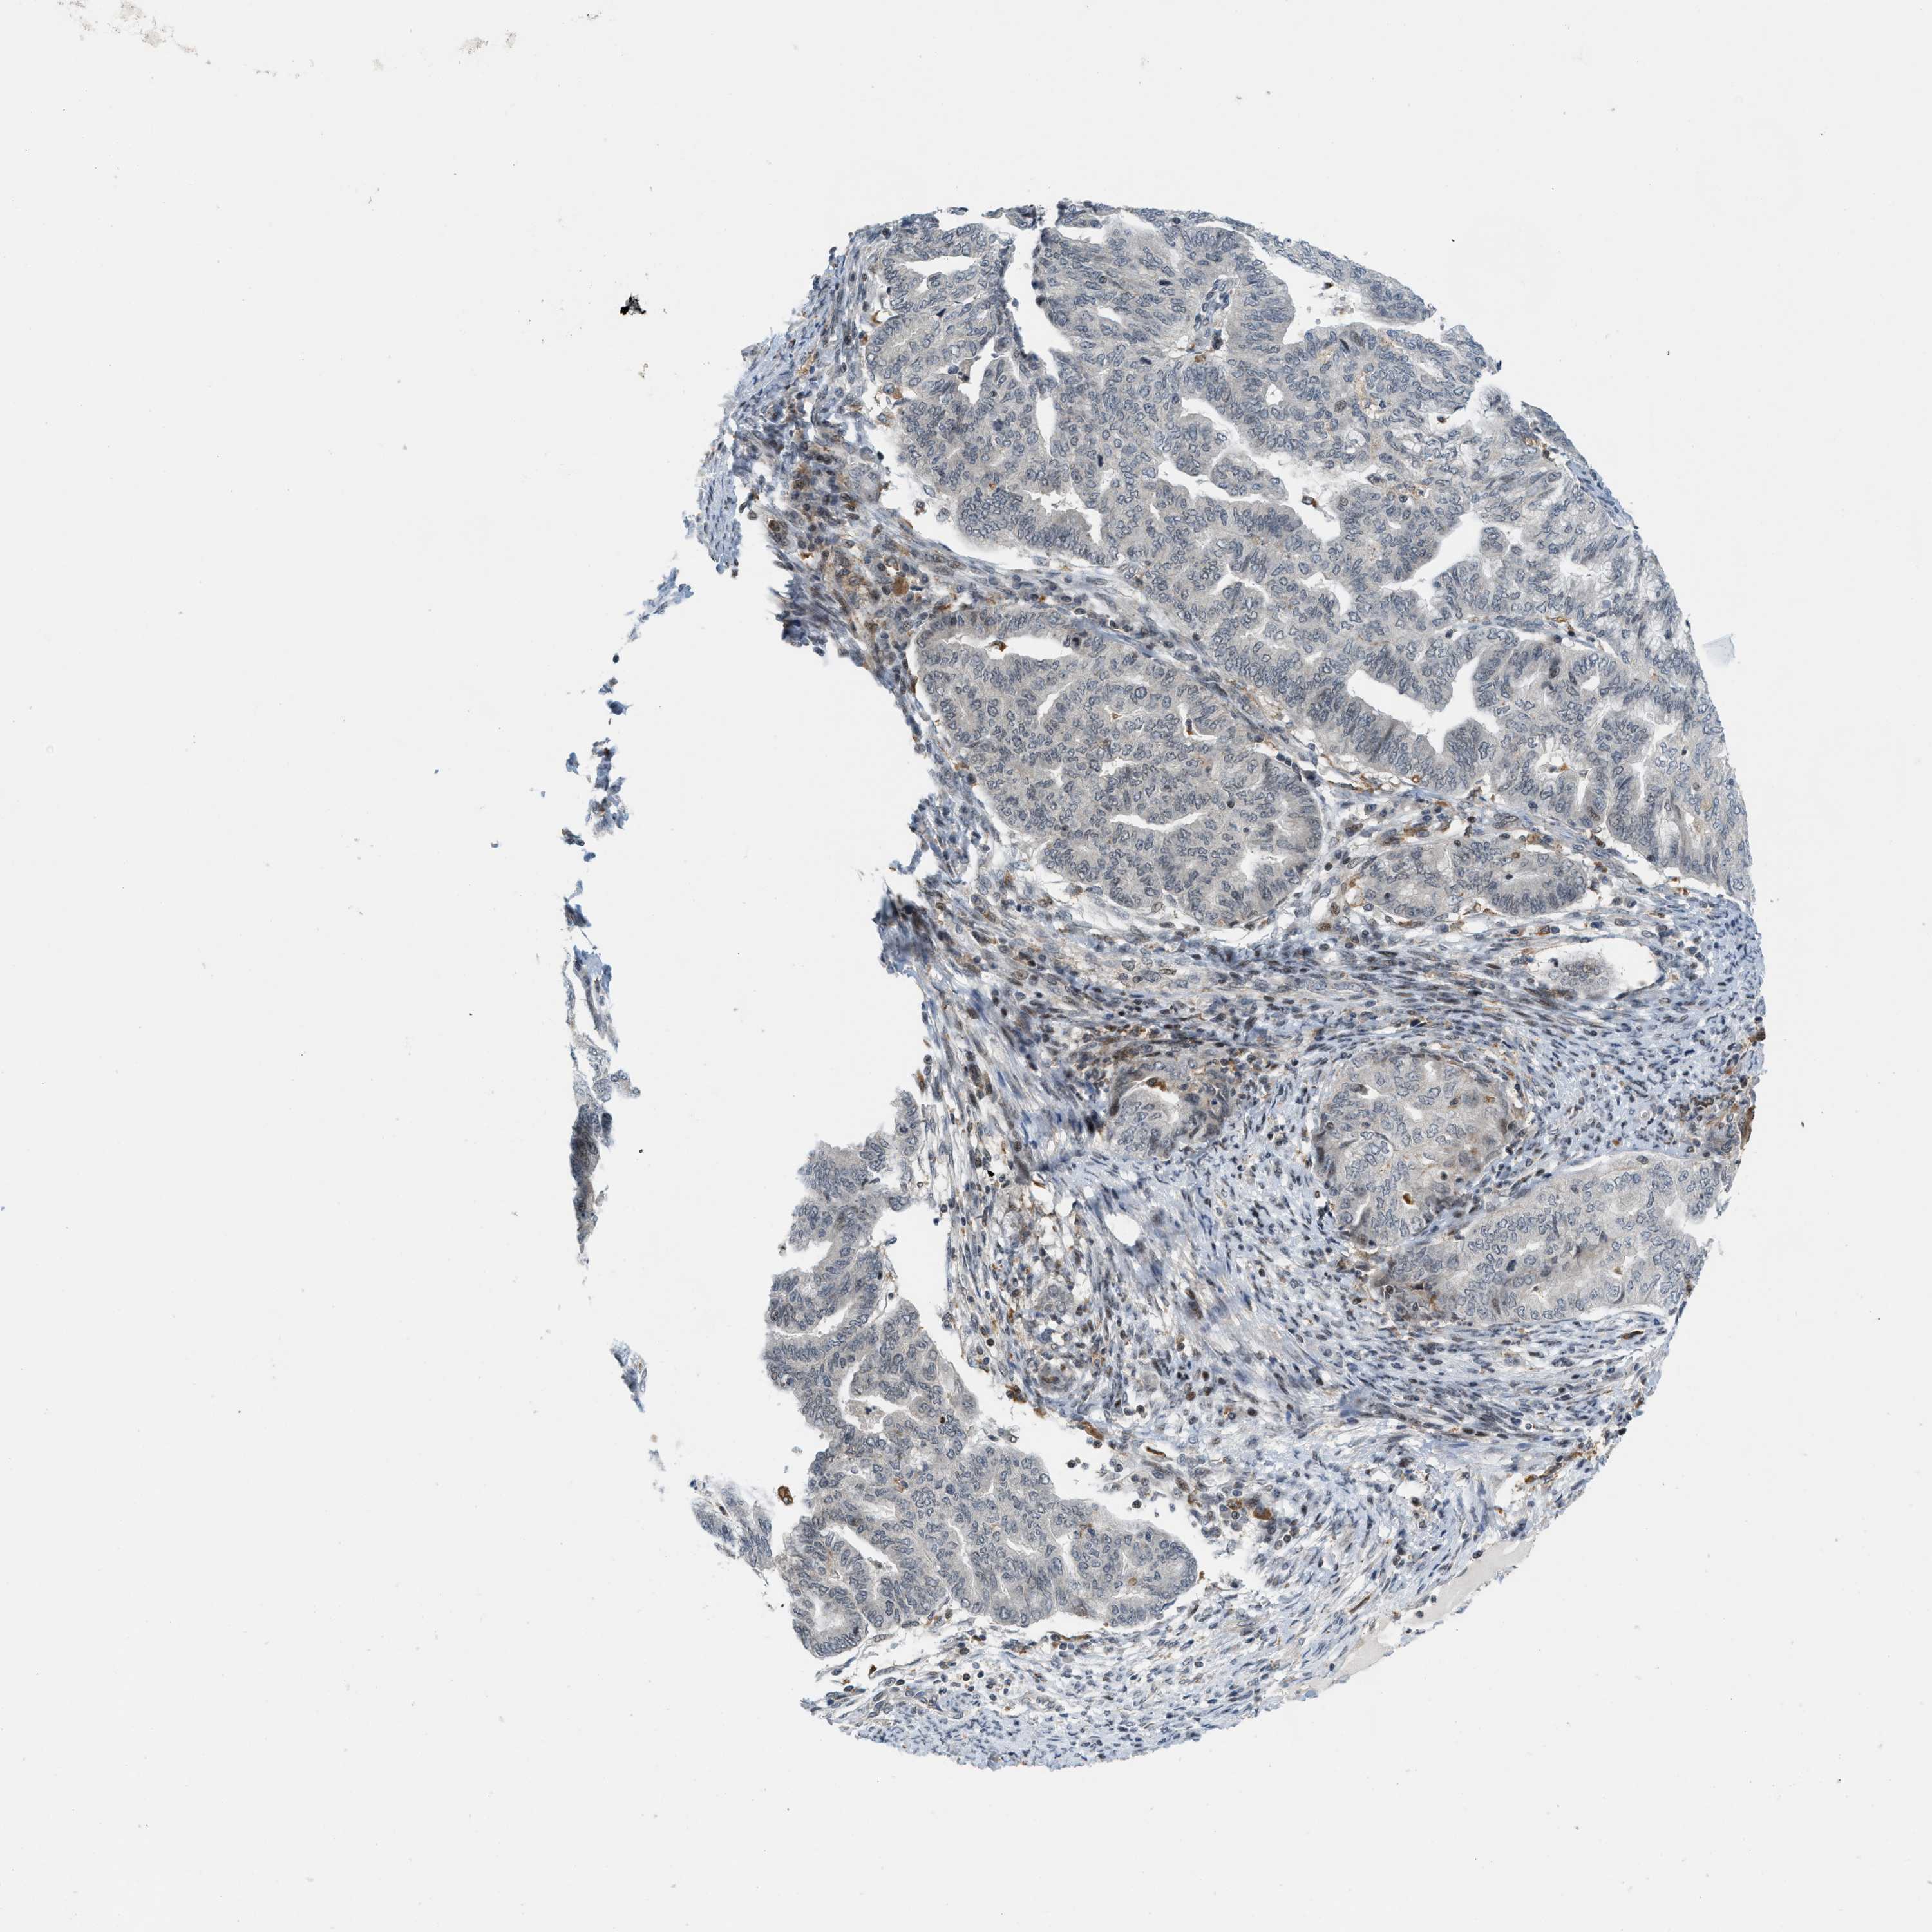

ENDOMETRIAL CANCER - Protein expressioni

A mouse-over function shows sample information and annotation data. Click on an image to view it in a full screen mode. Samples can be filtered based on level of antibody staining by selecting one or several of the following categories: high, medium, low and not detected. The assay and annotation is described here.

Note that samples used for immunohistochemistry by the Human Protein Atlas do not correspond to samples in the TCGA dataset.

Antibody stainingi

Antibody staining in the annotated cell types in the current human tissue is reported as not detected, low, medium, or high, based on conventional immunohistochemistry profiling in selected tissues. This score is based on the combination of the staining intensity and fraction of stained cells.

Each image is clickable and will lead to virtual microscopy that enables deeper exploration of all samples and also displays staining intensity scores, fraction scores and subcellular localization as well as patient and tissue information for each sample.

Antibody CAB016136

Antibody CAB017773

Staining

High

Medium

Low

Not detected

Intensity

Strong

Moderate

Weak

Negative

Quantity

>75%

75%-25%

<25%

None

Location

Nuclear

Cytoplasmic/membranous

Cytoplasmic/membranous,nuclear

Adenocarcinoma, NOS